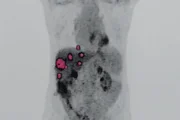

Ressonância que indicou presença de nódulos no fígado transplantado

Sete meses depois, Júnior apresentou sintomas de alterações hepáticas e foi submetido a uma ressonância magnética, que apontou a presença de seis nódulos no fígado transplantado. Após biópsia, foi constatado que o achado se tratava de um adenocarcinoma – um dos tipos de câncer mais comuns em adultos, que pode se desenvolver no trato gastrointestinal, nos pulmões, no sistema reprodutor e em outros órgãos.